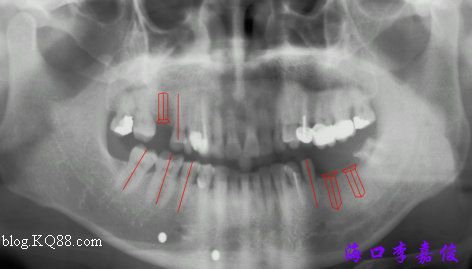

模擬圖分析,另還做了模型切開分析,以十分的準備應(yīng)對三分的工作不是一種浪費,而以三分的準備應(yīng)對十分的工作則可能會出現(xiàn)不可逆轉(zhuǎn)的惡果。

術(shù)前,17稍前傾